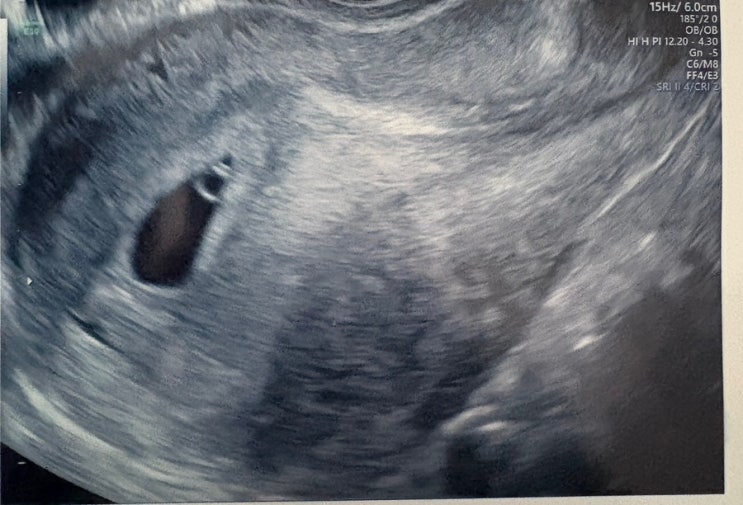

[임신일기]5주~13주 입덧 진행중

블로그를 열심히 쓰다가 이런저런 이유로? 핑계로 한동안 쓰지 못했다. (핸드폰 고장.. 컨디션 난조..) 그 ...